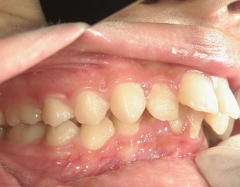

18歳女性 浜松市中区在住

治療期間3年11ヶ月

主訴:上の歯が前に出ている。

矯正歯科 治療前 左右上下4番  計4本抜歯

no.18_2196_治療前_右.jpgno.18_2196_治療前_正面.jpgno.18_2196_治療前_左.jpg